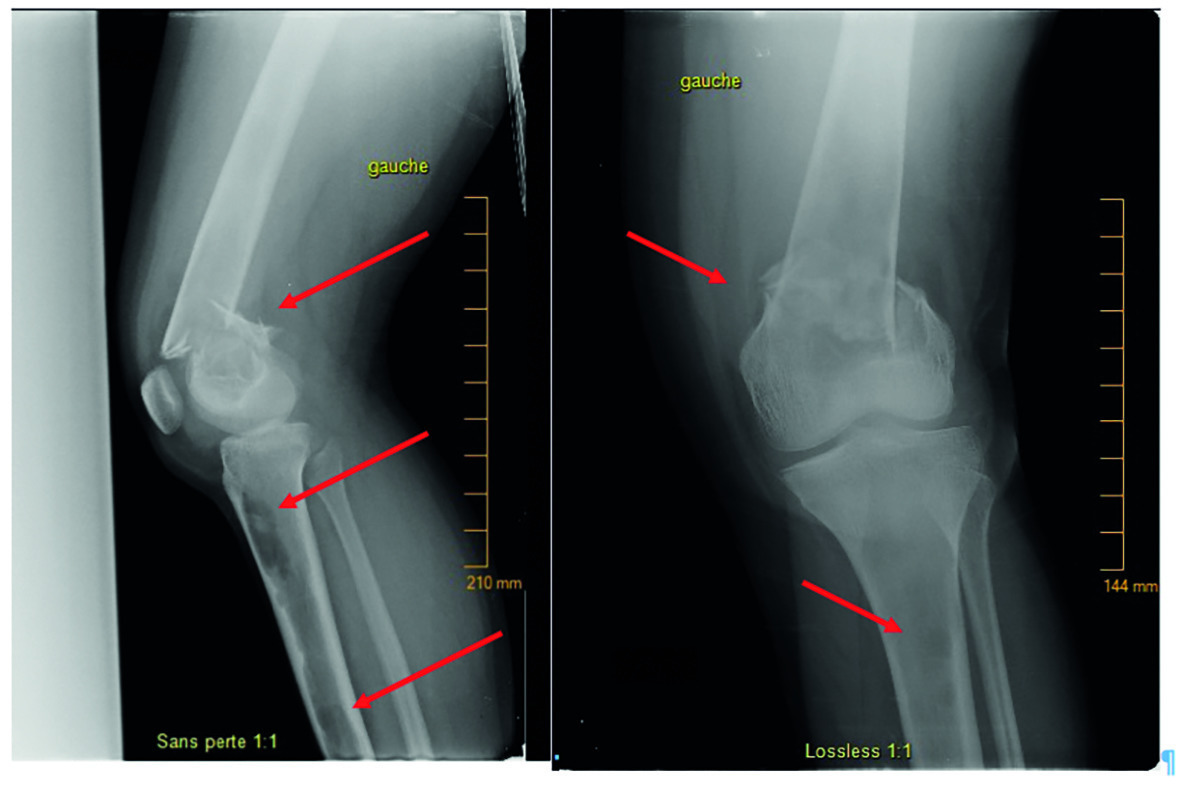

Les radios montrent une fracture fermée comminutive déplacée, supracondylienne, du fémur (fig. 1), dont la sévérité fait suspecter une pathologie sous-jacente. On note plusieurs lésions ovalaires hyperclaires et un amincissement de la corticale osseuse au niveau du tiers distal du fémur et du tibial proximal gauches (fig. 1 ; kystes lacunaires au scanner, fig. 2 ), mais aussi des lésions lacunaires bilatérales diaphysaires et métaphyso-diaphysaires.

Les radios montrent une fracture fermée comminutive déplacée, supracondylienne, du fémur (fig. 1), dont la sévérité fait suspecter une pathologie sous-jacente. On note plusieurs lésions ovalaires hyperclaires et un amincissement de la corticale osseuse au niveau du tiers distal du fémur et du tibial proximal gauches (